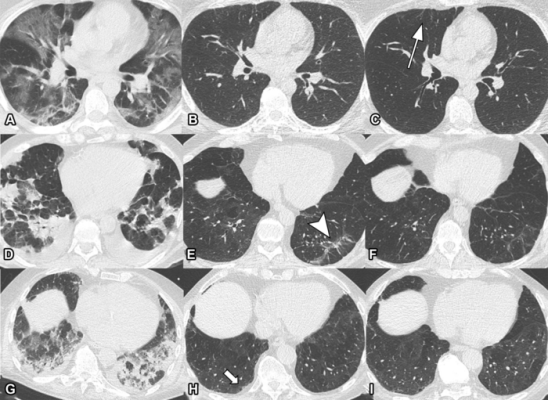

Serial non-contrast axial chest CTs of three study participants with prior COVID-19 pneumonia. Chest CT of a 44-year-old man (upper row, A-C) displayed extensive bilateral GGO and supleural reticulation during acute COVID-19 (A). At the 2-month follow-up almost complete resolution of GGO with residual subpleural reticulation in the middle lobe was noted (B). These subpleural reticulations (arrow) persisted up to one year after onset (C). Chest CT of a 68-year-old-man (middle row, D-F) demonstrated patchy bilateral consolidations, a subpleural arcade-like sign and pleural effusions during active infection (D). At the 2-month follow-up, a substantial improvement of OP pattern was noted with GGO and subpleural reticulation including arcade-like sign (arrowhead) in the left lower lobe (E). At the 1-year follow-up, further improvement was noticed. However, subtle reticulation and GGO could still be detected (F). Chest CT of a 79-year-old man (lower row, G-I) displayed bilateral consolidations and small areas of GGO while admitted to the ICU (G). At the 2-month follow-up, residual GGO and small subpleural microcystic changes (thick arrow) were noticed (H), which persisted up to 1 year after onset (I). Image courtesy of the Radiological Society of North America

March 29, 2022 — Some people recovering from COVID-19 pneumonia have CT evidence of damage to their lungs that persists a full year after the onset of symptoms, according to a new study published in the journal Radiology.

As part of an Austria-based observational study on the development of lung disease in patients with SARS-CoV-2 infection, researchers looked at patterns and rates of improvement of chest CT abnormalities in patients one year after COVID-19 pneumonia. CT has been an important imaging tool in the workup of patients suspected of having COVID-19.

The researchers assessed lung abnormalities on chest CT in 91 participants, mean age 59 years, at several points over one year after the onset of COVID-19 symptoms.

At one year, CT abnormalities were present in 49, or 54%, of the 91 participants. Of these 49 participants, two (4%) had received outpatient treatment only, while 25 (51%) were treated on a general hospital ward and 22 (45%) had received intensive care unit (ICU) treatment.

“The observed chest CT abnormalities from our study are indicative of damaged lung tissue,” said study co-author Anna Luger, M.D., from the Department of Radiology at Innsbruck Medical University in Innsbruck, Austria. “However, it is currently unclear if they represent persistent scarring, and whether they regress over time or lead to pulmonary fibrosis.”

While CT abnormalities decreased in initial follow-ups, 63% of participants with abnormalities did not show any further improvement after six months. Age over 60 years, critical COVID-19 severity and male gender were associated with persistent CT abnormalities at one year.